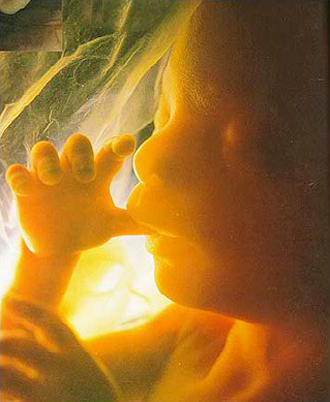

- 필수 검사

- 복부 초음파 (1회/4주)

- 중기 정밀 초음파

(태아 내부장기 및 근골격 기형 등을 검사)